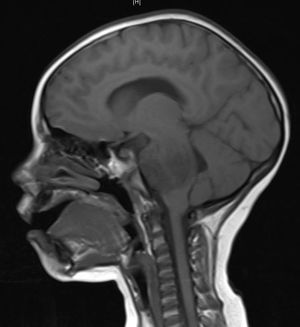

A brainstem glioma in four year old. MRI sagittal, without contrast